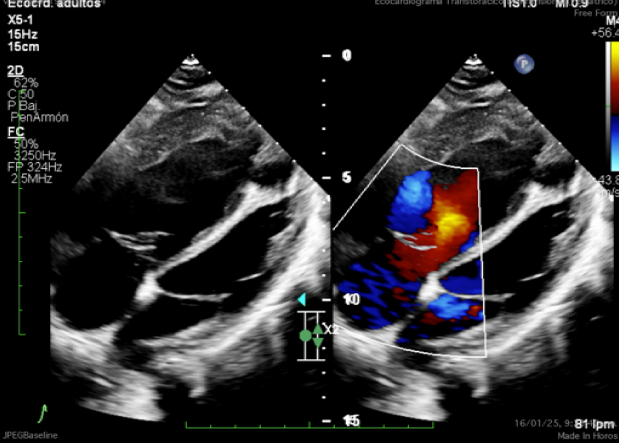

We describe a case of a male patient with left-sided CDH diagnosed prenatally and surgically repaired in the neonatal period. He developed severe PH requiring extracorporeal membrane oxygenation (ECMO), prostaglandins, and prolonged dual therapy with endothelin receptor antagonists (bosentan, macitentan). He was weaned off oxygen at age 3 but required re-initiation at 17 due to progressive desaturation. Additional congenital anomalies included repaired aortic coarctation and multiple abdominal surgeries. At age 20, clinical deterioration followed the introduction of selexipag, with worsening hypoxemia, increased oxygen requirements, and suspicion of pulmonary vascular disease progression. Cardiac catheterization and cross-sectional imaging were attempted but were limited by profound hypoxemia and instability.

Descriptive findings revealed resting oxygen saturations of 82–85% on 4 L/min supplemental oxygen, WHO functional class III, and echocardiographic signs of right ventricular overload. Laboratory markers showed elevated NT-proBNP (1,347 pg/mL). No evidence of acute thromboembolism was found. Clinical worsening was temporally associated with selexipag initiation. Drug withdrawal led to partial functional and oxygenation recovery. Based on clinical trajectory and ancillary testing, Group 3 PH secondary to developmental lung disease was the working diagnosis. The case was discussed at a national PH board, confirming the suspicion of irreversible pulmonary vascular compromise.